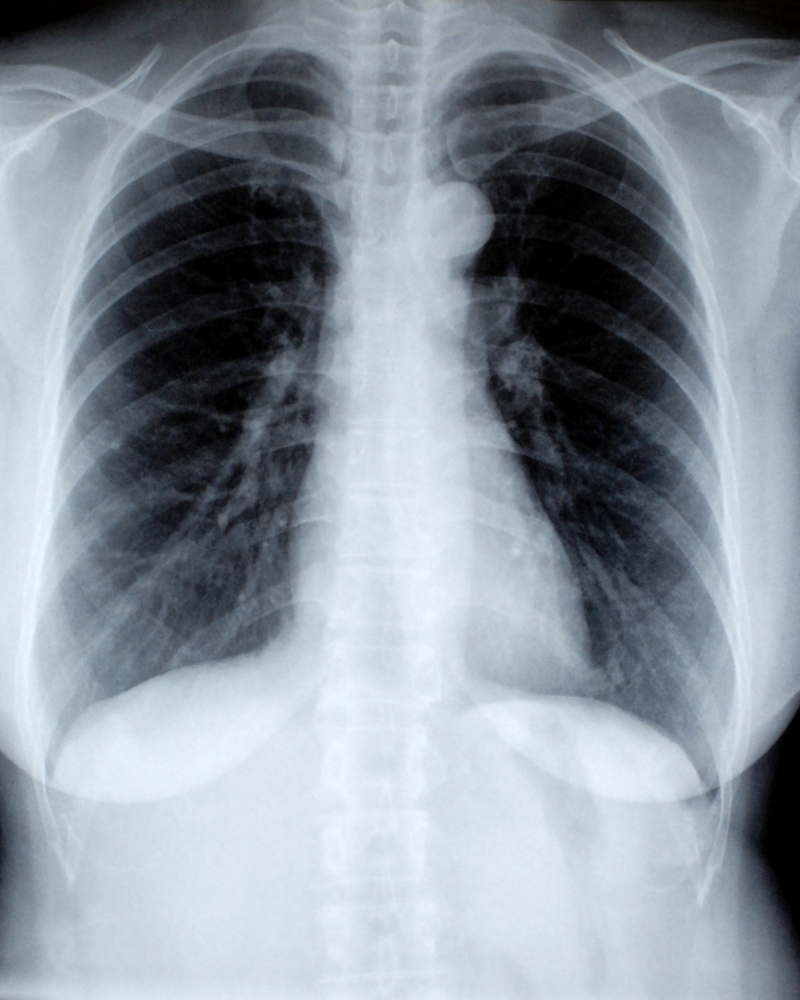

The X-ray Thoraco Lumbar Extension is a specialized diagnostic imaging test that captures detailed images of the thoraco-lumbar region—the junction between the thoracic and lumbar spine. This scan is performed with the spine in an extended position to assess spinal movements, detect abnormalities, and evaluate vertebral alignment.

At Diagnopein, we use advanced digital radiography systems to deliver clear, precise, and high-quality X-ray images that help in accurate diagnosis of spinal disorders. This test plays a vital role in evaluating the stability and flexibility of the spine, especially after trauma or surgery.